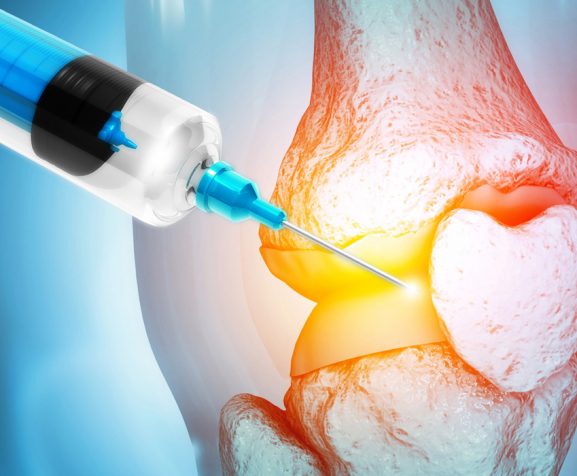

Arthritis

Joint Instability